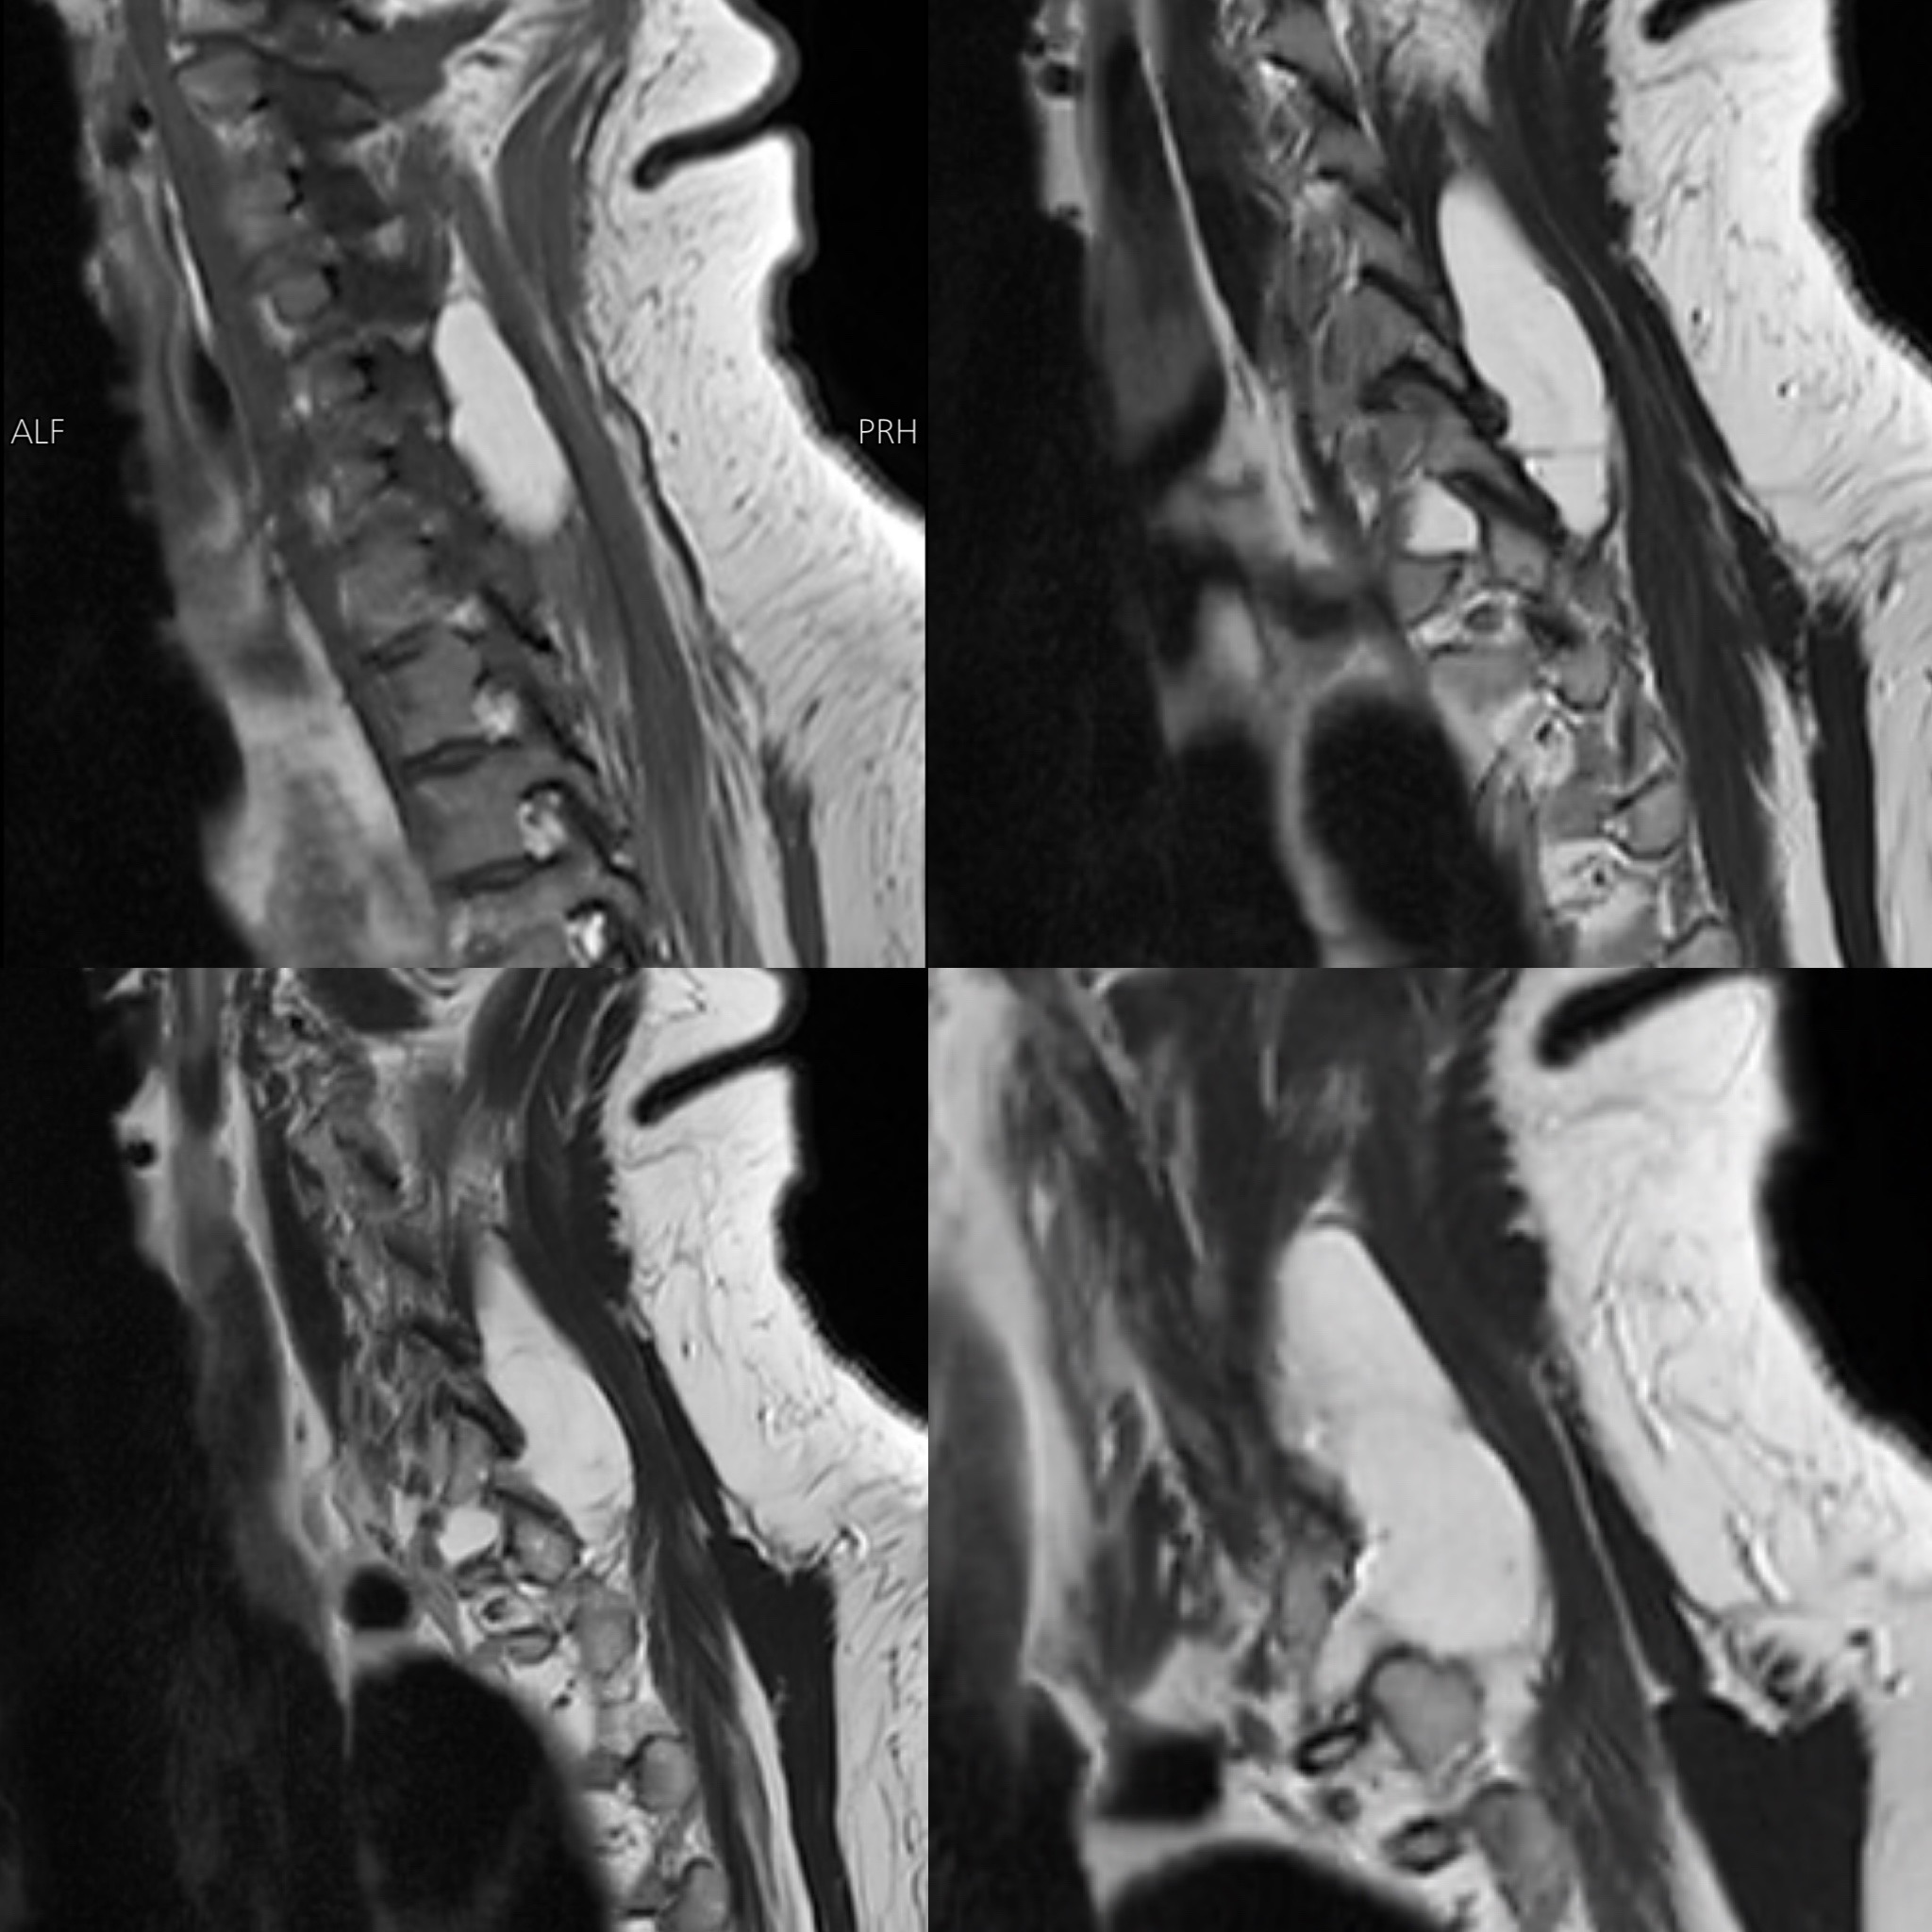

MRI Cervical Spine (31 Jan 2026 — House of Diagnostics, Indirapuram)

- Multilevel cervical spondylosis with disc bulge and annular tears at C4-C5, C5-C6, and C6-C7, causing bilateral foraminal narrowing and mild nerve root impingement (right > left)

- Mild disc changes at C2-C3 and C3-C4 without nerve root impingement

- Straightening of cervical lordosis with mild dextroscoliosis

- Cervical spinal cord: Normal — no signal change, no myelopathy

- A lobulated, well-defined T1/T2 hyperintense lesion in the right posterior paravertebral muscles, extending from C4-C5 to D1 level, measuring 40 × 20 × 54 mm — showing complete fat saturation on STIR sequences, consistent with a benign intramuscular lipoma (a non-cancerous fatty tumour within the muscle), with extension into the right paravertebral gutter and C7-D1 neural foramen causing nerve root compression, but no intraspinal extension and no cord involvement

The cervical spine findings explained her neck pain, but did not account for her acute vertigo presentation. The cord was normal, making cervical myelopathy an unlikely contributor to her primary complaint.